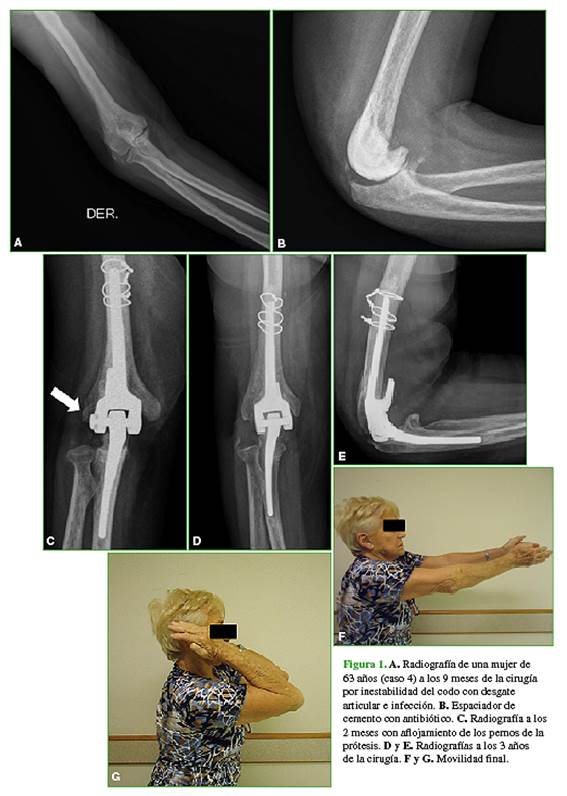

Un paciente (caso 4) presentó un aflojamiento de los pernos por una falla técnica en la inserción a los dos meses de la cirugía, y necesitó una nueva operación para su correcta colocación (Figura 1). Por otro lado, se detectó una necrosis del colgajo con recurrencia de la infección en un paciente (caso 8). Salvo este último paciente, todos tuvieron parámetros bioquímicos normales en el posoperatorio y no se detectó una reactivación de la infección en el último seguimiento.

Al evaluar a los pacientes según su stock óseo, cinco fueron incluidos dentro del grupo A y cinco, dentro del grupo B (Figuras 2 y 3). El grupo A tenía menos cirugías previas y obtuvo mejores resultados funcionales, principalmente en la recuperación de la fuerza de extensión, que el grupo B (Tabla 3).